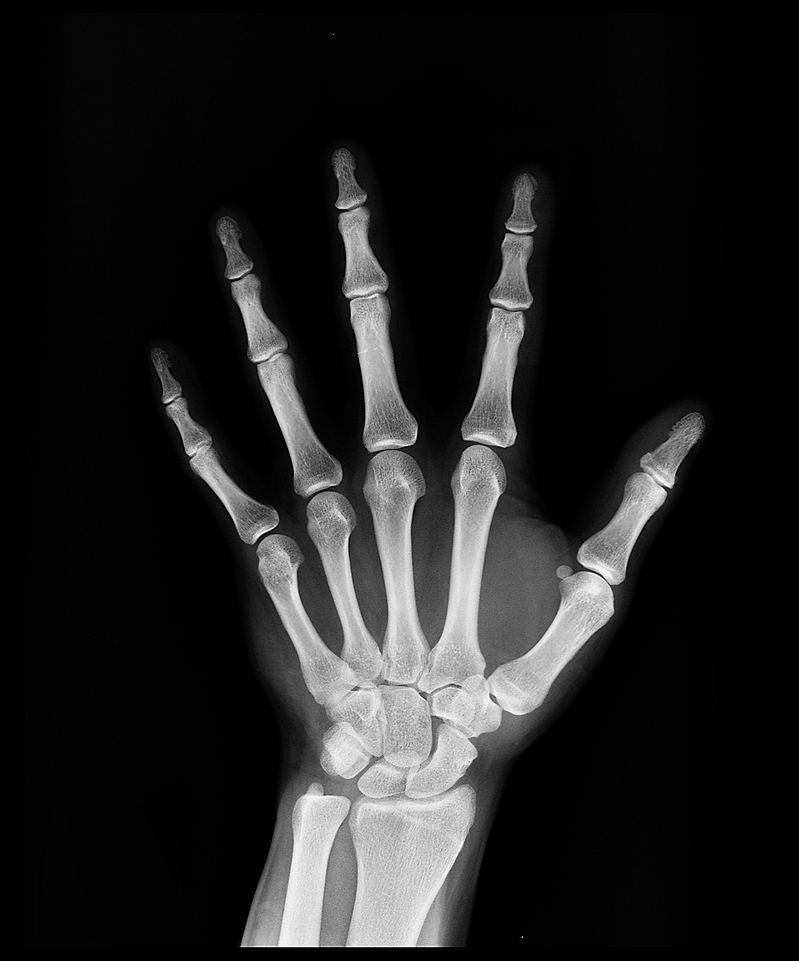

Throughout my career as a Diagnostic and Interventional Radiologist, I have been asked numerous times by family and friends to help them understand just what their Radiology study is showing and more importantly what impact the findings would have to their overall health. More often than not, they could not make sense of the actual pictures and really never understood the medical jargon used in the accompanying Radiology report. What the heck does "Unremarkable", "Hypoattenuation", "BI-RADS 3" or "FDG avid" even mean?

Only a few short years ago, the audience of the radiology report generated by a Radiologist was the physician that referred the patient for medical imaging. Therefore, the report was worded in a very technical fashion using medical terminology rarely understood by the general public. Well what has changed over the last few years? Direct access of patients to their radiology reports and actual images through their online portals has been both a blessing and a curse. Patients can now easily read their report and pull up the corresponding images ill-equipped to actually understand the appearance or wording which can lead to more anxiety, fear and potentially unnecessary worrying.

Education of patients has always been a passion of mine! Whether it be a family member with newly diagnosed cancer consumed by anxiety and fear or a friend who tore their Achilles tendon concerned about an impending surgery, some of the greatest joy in my career has been derived from that inevitable phone call or quick get together over a cup of coffee describing how radioactive "sugar" can be used to detect cancer on a PET scan, explaining step-by-step how a biopsy is performed or pointing out the appearance of a torn meniscus on MRI. For in that moment, I was able to appreciate the undeniable impact all the knowledge gained over 25 years in medicine could have on those seeking more information. Using a basic anatomic approach and plain language, I found that fears could be quelled and informed healthcare decision making could be empowered.

There are services available online for Radiology "second opinions" costing between $199 and $500 per opinion; however, one thing is missing from these offerings, direct interaction with an actual Radiologist. I believe the added personal touch has been the missing link in the delivery of Radiology services for the last many decades. Now more than ever it is needed. BareBones Radiology is more than just a second opinion. We focus on tailored, one-on-one consultative image review directly with clients wishing to gain a better understanding of their medical imaging allowing for more informed healthcare decision making and ultimately less anxiety and fear.